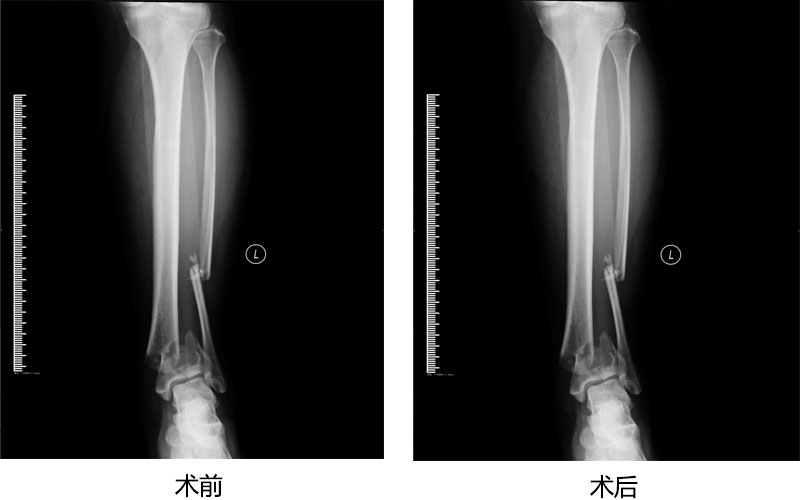

胫腓骨远端骨折传统手术

骨折传统手术治疗技术已炉火纯青,达全国领先水平;骨折微创手术也已广泛应用,紧跟着国际步伐。我们以精堪的技术为广大病人群众提供优质服务。